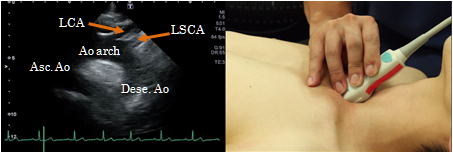

Suprasternal aortic arch view

To obtain a suprasternal aortic arch view, place the patient in the supine position with his/her neck extended backward and place the probe on the suprasternal space. This view shows the ascending aorta, the aortic arch with its branches and the descending aorta. It is suitable for observation of aortic dissection and aortic aneurysm.